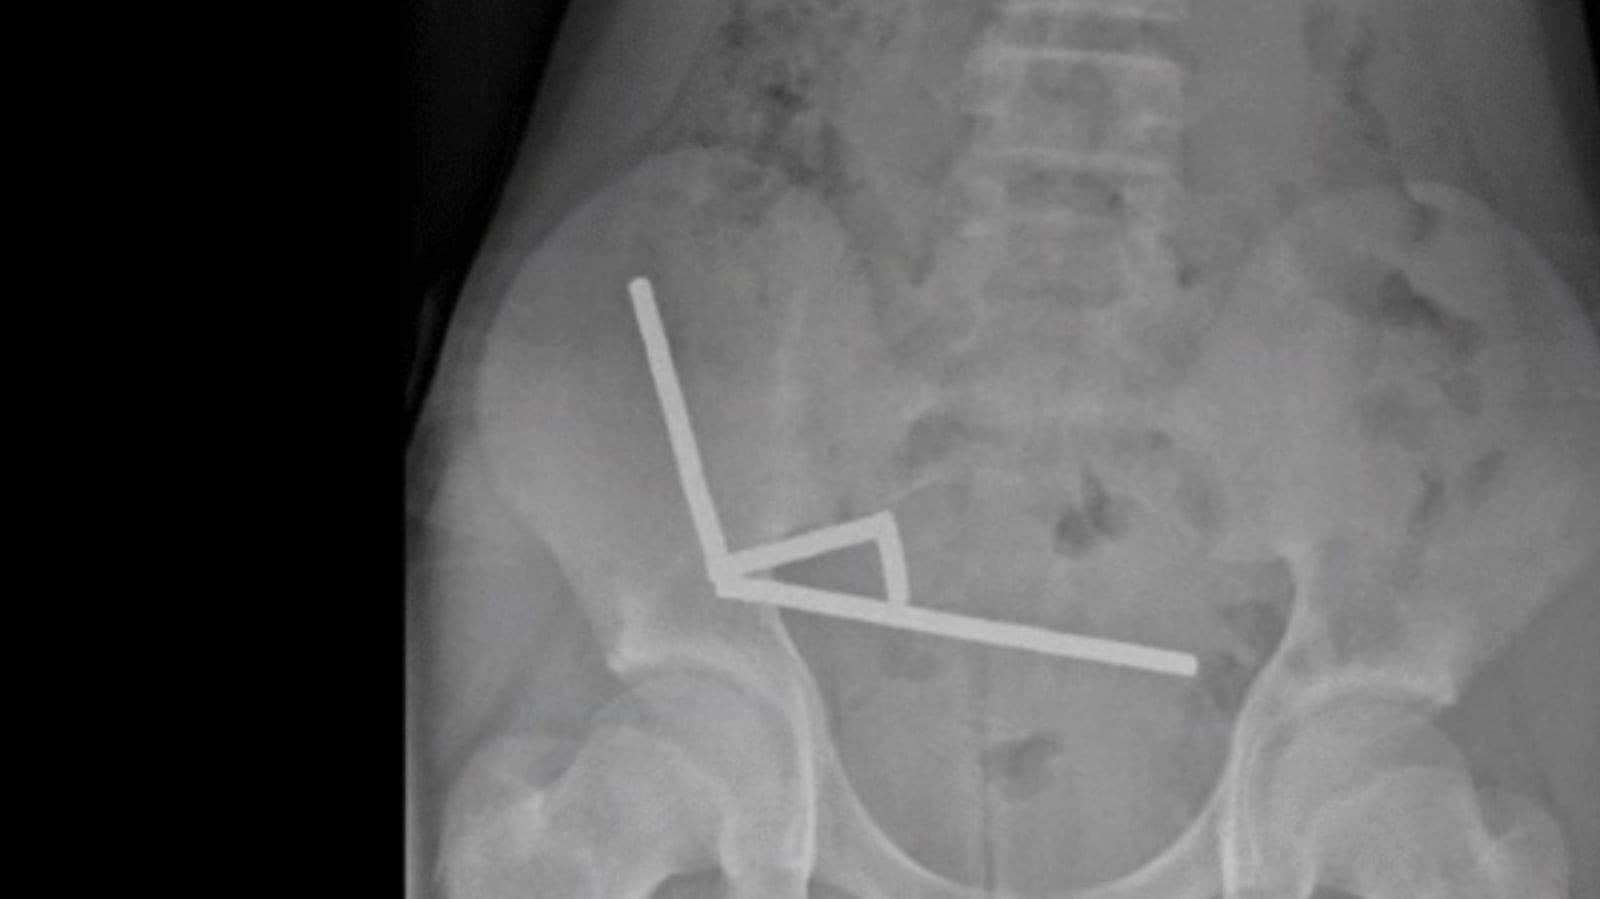

ニュージーランドで、13歳じゅうさんさいの男おとこの子こが強つよい磁石じしゃくを80個こぐらい飲のみました。お腹なかが痛いたくなって、病院びょういんで腸ちょうの一部いちぶを切きる手術しゅじゅつを受うけました。

男おとこの子こが飲のんだのは、ネオジム磁石じしゃくです。とても強つよい磁石じしゃくで、大人おとなが使つかうために売うっています。飲のむと、磁石じしゃくが腸ちょうなどを引ひっ張ぱって、穴あながあいたり、死しんでしまったりすることがあります。